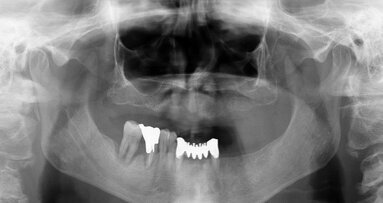

G. I. paziente di anni 50, si presenta alla nostra osservazione con una frattura longitudinale della radice dell’elemento 4.5 dovuta a infiltrazione cariosa della vecchia corona protesica. Questa situazione ha provocato nell’osso alveolare del paziente una grossa lesione che è andata ad interessare anche la corticale vestibolare. Per poter sostituire la radice con un impianto sarebbe necessario un intervento di chirurgia ossea rigenerativa ma un’alternativa meno invasiva è la rigenerazione del tessuto osseo ottenuta tramite l’estrusione forzata dell’elemento che rigenera osso durante la sua lenta migrazione grazie al legamento parodontale. In accordo con il paziente, dopo opportuna spiegazione dei benefici e dei tempi dell’approccio con estrusione ortodontica, si decide di procedere con questo iter evitando così l’intervento di rigenerativa.

L’estrusione completa del frammento ha richiesto un tempo di 6 mesi, durante i quali è stata modificata più volte l’inclinazione della molla per evitare che il movimento diventasse ortogonale al segmento e mantenere la traiettoria prevista. Così facendo, è stato possibile rigenerare naturalmente l’intero alveolo e inserire, dopo 3 mesi di ulteriore maturazione del tessuto, in un contesto osseo ideale e perfettamente rigenerato un impianto Syra (Sweden & Martina) di diametro 4.25 mm e lungo 11 mm.

Dopo 3 mesi dall’inserimento implantare è stato possibile prendere un’impronta e di precisione e realizzare una corona singola avvitata.